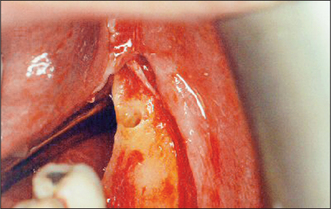

Excision of a maxillary or mandibular torus

A torus (Figs 11.13, 11.14) is a developmental bone exostosis, present typically either on the midline of the hard palate or on the lingual aspect of the mandible above the mylohyoid ridge (usually bilat-erally). Patients are often unaware of their existence. There are other causes of bony expansion of the jaws, some of which may have a history of slow onset and gradual enlargement. A neoplastic lesion (usually of minor salivary gland origin) sometimes develops on the hard palate, and it has been known for a dentist to ease a denture to accommodate an enlarging malignant growth. If there is doubt about the nature of any lesion, the patient is referred for a specialist opinion.

image

Fig. 11.13 Lingual tori are typically bilateral, although the patient is often unaware of their existence.

A denture rubbing on a torus may cause ulceration of the overlying oral mucosa and pain. Removal of a torus may therefore be indicated if the denture cannot be constructed to avoid it.